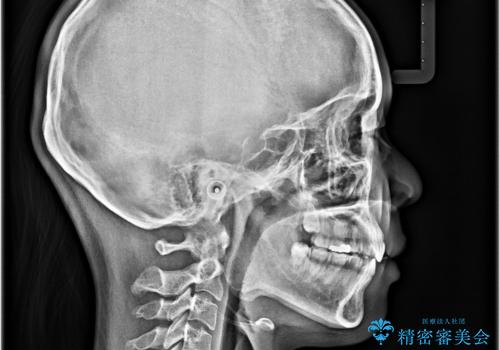

- 下顎小臼歯が欠損しており、さらに上顎が全体的に突出していることを気にして来院された患者様です。

下顎は片方の小臼歯が欠損していたため、正中がずれた上に、上下前歯が接触していない状態でした。

上顎左右の小臼歯2本および下顎小臼歯を1本抜歯し、補助装置を用いて上顎大臼歯が前方に移動しないように固定した上で、ワイヤー装置にて矯正治療を行うこととしました。

上下前歯のズレは舌の突出癖による影響も大きいと考えられたたため、舌のトレーニングをしっかりと行っていただきました。